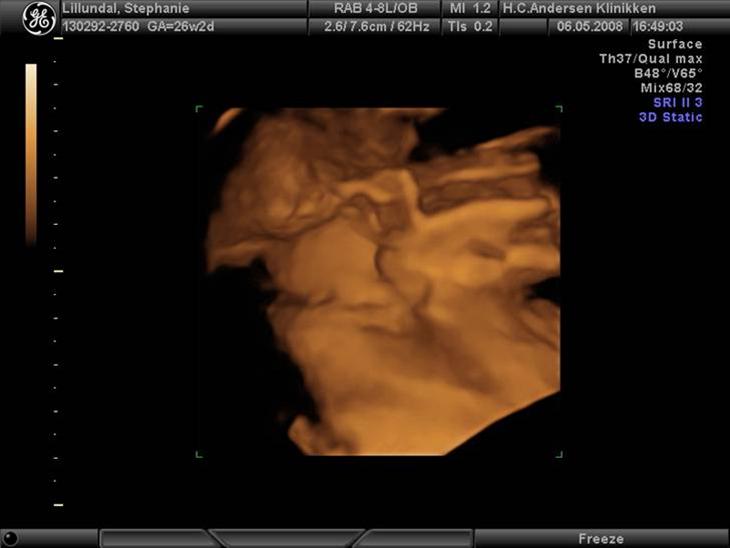

Lille Victoria inde i maven i uge 26.